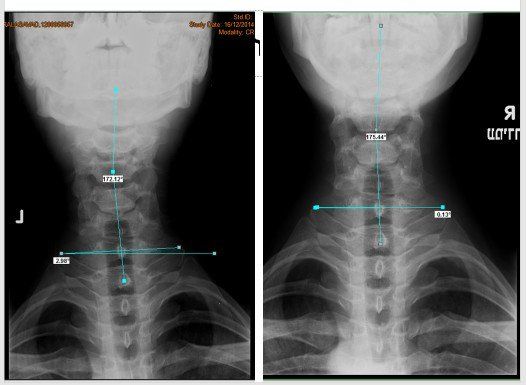

ื"ืจ ื ืืืื ืงืืืข ืืช ืชืืื ืืช ืืืืคืื ืืืืืืฆืช ืืืชืื ืืืกืืืจืื ืืจืคืืืืช, ืืืฆืื ืืืืืงืืช, ืืืฆืื ืจื ืืื, ืกื-ืื ืื ืื-ืืจ-ืืื, ืืืฉืืฉ ืืืืืืช ืืืืืืจ ืฉื ืคืืข ืืืืืื ืืืจืืคืจืงืื ืืื ืืืขืจืื ืขื ืืื ืืฉืคืืข ืื ืืง ืืขืืื ืืฉืืืจื ืขื ืืขืจืืช ืืขืฆืืื ืืืจืืืืช ืืืืฃ. ืืฉืื ืืืืืจ ืฉืชืคืงืื ืืืืจืืคืจืงื ืืื ืืืกืืจ ืกืืืืงืกืฆืื (ืชืช ื ืงืืขื ืฉืืจืชื) ืฉืืคืจืืข ืืืืฃ ืืชืคืงื ืืืืคื ืืืคืืืืื. ืชืืืื ืจืืคืื ืืจืงืืืช ืืื ืืืขื ืืืชืืคืฉืจ ืืชืื ืืืืฃ ืขืฆืื. ืืืืฃ ืืฉ ืืืืืช ืจืืคืื ืืืขืืช ืืืืืืขืช ืืืจืงื ืืื ืื ืืฉืื. ืืืืืื ืืืืจืืคืจืงืื ืืกืืจ ืืืฅ ืืืืขืจืืช ืืขืฆืืืช ืข"ื ืฉืืคืืจ ืชืคืงืื ืขืืื ืืฉืืจื, ืืืืคืฉืจ ืืื ืจืืื ืืขืฆืืืช ืืืฉืชืืฉ ืืืืืืืช ืืืืฃ ืืืืขืืืช ืืืืืื. ืจืคืืื ืืืชืืช ืชืืื ืืื ืืืื ืืืืื ืืชืื ืืืืฃ ืขืฆืื. ืชืงืฉืืจืช ืืื ืืืื ืืืืฃ ืืืืจื ืืื ืืืืฃ ืืืื ืืืื ืืช ืืงืืื ืืืืฃ ืืืจืืืืชื. ืคืืื ืฆืืื ืืืจืืืืช ืืืืืช ืื ืจืืืืช ืืืืื ืฉืืืืฃ ืืืื ืืืืืข ืชืืืืื ืืืจืืืืช ืขืืื ืืฉืืจื ืืืืขืจืืช ืืขืฆืืืช ืฉืคืืขืืื ืืื ืืคืจืขืืช ืืืชืืื.

ืืืืคืื ืืืืจืืคืจืงืื ืืืื ืืช ืืืืฃ ืืืืจืืฅ ืืช ืื ืจืืืืช ืืืืื ืืชืืื ืืืืืื.